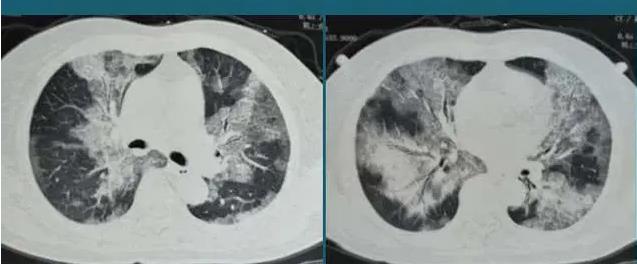

白肺 , 是下呼吸道感染后出现的一种症状 , 其真实的情况就是肺部感染 , 而不是肺的颜色变白 , 随着白肺报道的逐渐增多 , 前去CT室拍片“为求心安”的人也越来越多 。

但实际上 , 白肺并不是这样 , 白肺就是下呼吸道感染 , 肺内有炎症罢了 。